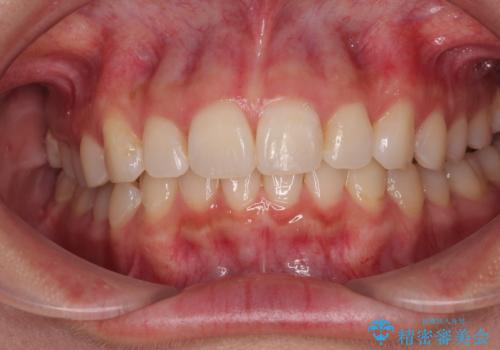

前歯の捻れを改善するとともに、口元が少しでも引っ込むように治療計画を立て、仕上げることができました。

長時間の装着を徹底し、遠方からの通院にもかかわらずしっかりと通院いただき、予想よりも早く治療を終えることができました。